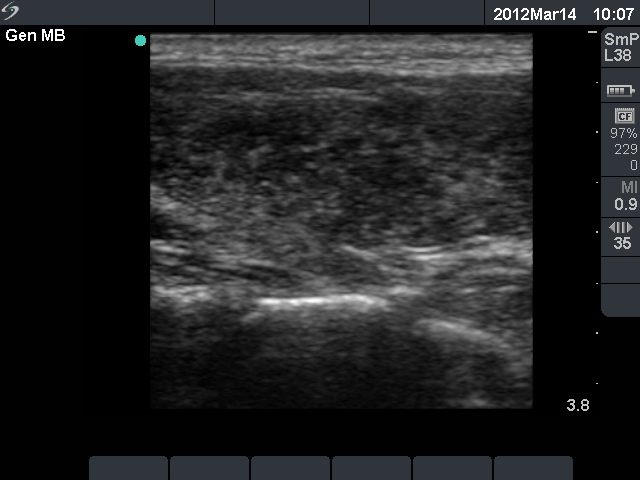

Six months after initial investigation (second row):

Clinical presentation: she had no complaints till the last several week, then she noticed increase in heart rate and fatigue.

Palpation: both thyroids were enlarged.

Functional state: hyperthyroidism with TSH-level 0.09 mIU/L, FT4 28.2 pM/L, FT3 12.8 pM/L.

Ultrasonography: the thyroids were hypoechogenic and presented increased vascularization.

Clinical diagnosis: recurrent hyperthyroidism caused by Graves's disease. We administered daily 20 mg methimazole. 2 months later when FT4 level has normalized the patient underwent radioiodine therapy.